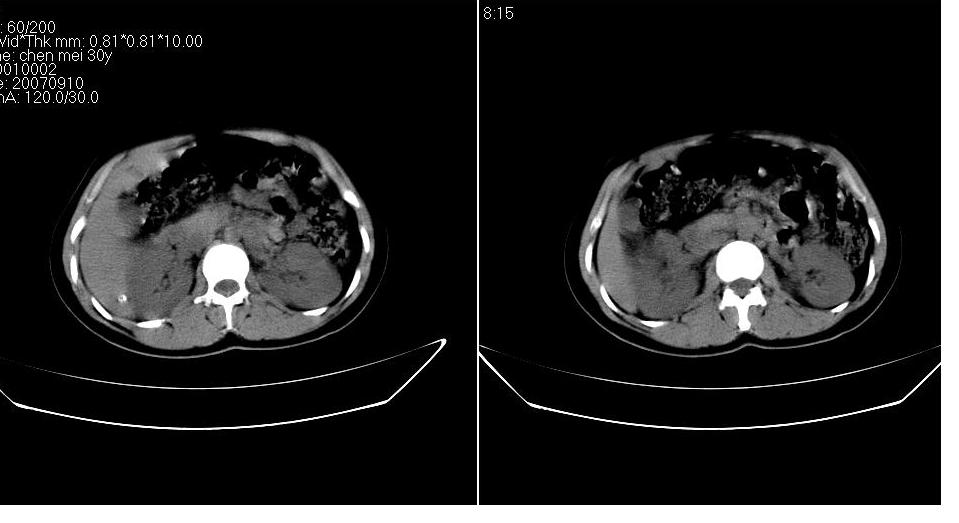

以下是引用求知若渴在2007-9-10 20:08:00的发言:[br]病变以脂肪成分为主,应该是错构瘤。另肝内胆管结石

以下是引用xulianj在2007-9-10 20:51:00的发言:[br]错构瘤,支持。含脂肪成分较多,证明较为成熟。

以下是引用齐原在2007-9-10 20:10:00的发言:[br]病变以脂肪成分为主,应该是错构瘤。另肝内胆管结石

以下是引用王仕学在2007-9-10 21:34:00的发言:[br]有脂肪密度,哪怕是一点点,首先考虑错构瘤。还是增强吧,好说些!